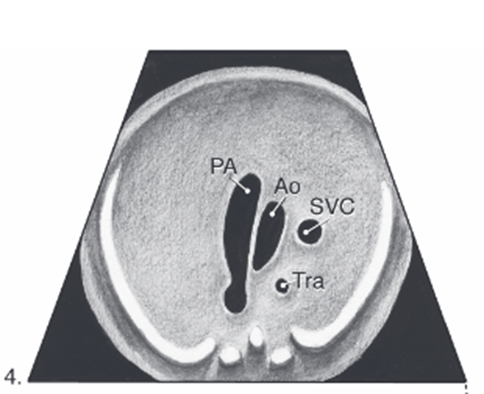

pulmonary artery comes out of ???

right ventricle

pulmonary artery quickly passes _____ and ____ of ascending aorta

anterior and left

right pulmonary artery passes ____ to the aorta

posterior

what does pulmonary artery split into

right and left pulmonary artery and ductus arteriosus

right pulmonary artery goes _____ aorta

behind

MPA always ____ or ____ ____ than aorta

equal or slightly bigger

3 vessel view (3VV)

pulmonary artery and aorta junction

ductus arteriosus

Where pulmonary artery and aorta join (ductus arteriosus) in the 3VT view is sometimes also referred to as the

transverse arches